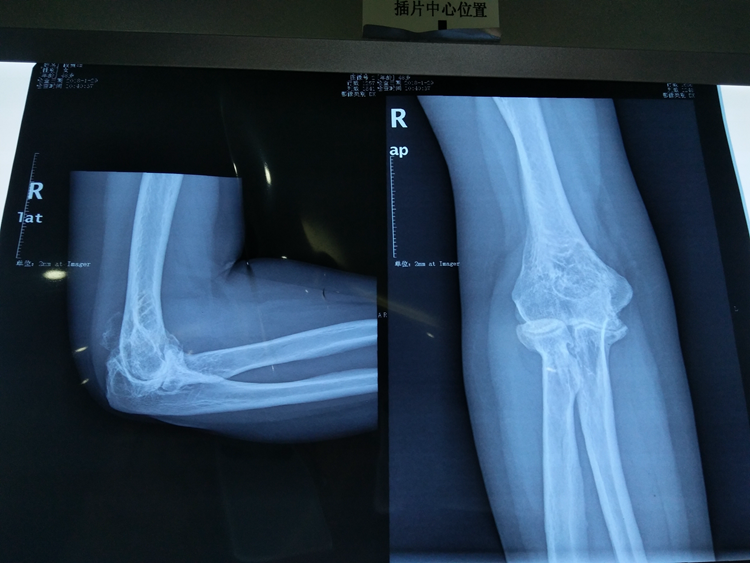

据了解,该患者15年来一直饱受右侧肘关节疼痛、活动障碍的困扰,近一个月来疼痛加重,生活起居严重受限。入院行相关检查后诊断为重度骨关节炎伴屈曲畸形,我院骨伤科手术团队经过反复分析与研究,决定为该患者施行右侧人工全肘关节置换术,仅用两小时成功完成手术。

与其它人工关节相比,全肘关节置换术是目前世界上开展相对较少的手术,对手术医师的操作准确性要求非常高,并且对软组织平衡及假体的匹配要求非常精准,但施行人工全肘关节置换术能极大地减少患者痛苦,降低经济负担,并缩短病程时间,同时这也是我院骨伤科手术团队在累计完成数百例髋、膝关节置换及肩关节置换手术的基础上开展的新手术方法,标志着我院院骨伤科在肘关节疾病手术治疗技术方面达到国内先进水平,为我市肘关节病人提供新的治疗方案,填补了我院肘关节置换方面的空白。(投稿/骨伤科 杨经慧)